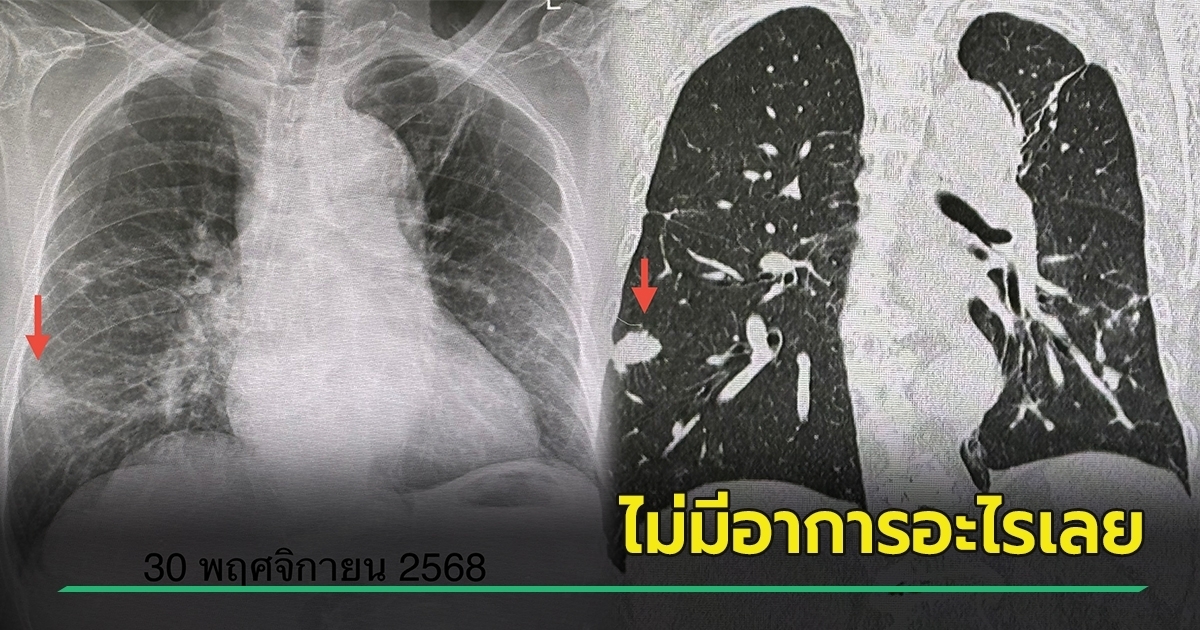

ผู้ป่วยรายนี้ มาตรวจร่างกายประจำปี ตรวจร่างกาย ไม่มีไข้ ฟังปอดปกติ เอกซเรย์ปอด มีเงาผิดปกติปอดข้างขวาด้านบนจากเคยป่วยเป็นวัณโรค และมีก้อนขนาด 1.9 x 1.9 เซนติเมตรที่ปอดข้างขวาด้านล่าง (ดูรูป) ก้อนนี้เป็นก้อนใหม่เพิ่งพบครั้งแรก ปีที่แล้วไม่มีก้อน ทำคอมพิวเตอร์ปอด พบก้อนขนาด 3.0 × 2.4 × 2.0 เซนติเมตรที่ปอดข้างขวาด้านล่าง ตรวจเลือด ค่ามะเร็งทุกตัวปกติ

เมื่อเจาะก้อนด้วยเข็ม ส่งชิ้นเนื้อตรวจพยาธิวิทยา พบปอดอักเสบจากเชื้อราคริปโตค็อกคัส ตรวจเลือดหาคริปโตค็อกคัสแอนติเจนให้ผลบวก titer 1 : 20 ทำคอมพิวเตอร์สมอง และเจาะน้ำไขสันหลังปกติ ไม่พบเชื้อราคริปโตค็อกคัสกระจายเข้าเยื่อหุ้มสมอง

วินิจฉัย : ปอดอักเสบจากติดเชื้อราคริปโตค็อกคัส